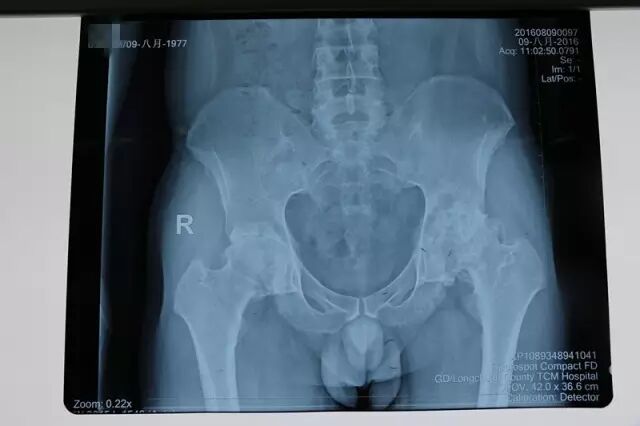

↑图:术前拍片

8月底,我院骨伤二科收治一名患有双侧股骨头无菌性坏死伴有强直性脊柱炎男性患者,经过科室及医院相关科室医生们对病情的会诊讨论,拟定了治疗方案。

9月4日,由肖智青主任、刁鉴伟主任,陈志强、赖卓志主治医师等组成的医师团队为该患者进行了双侧人工全髋关节置换术。术中成功避开了体位摆放困难、出血量大及神经损伤等风险,不但减少了患者二次手术的痛苦及风险,而且加快了患者术后恢复的速度。